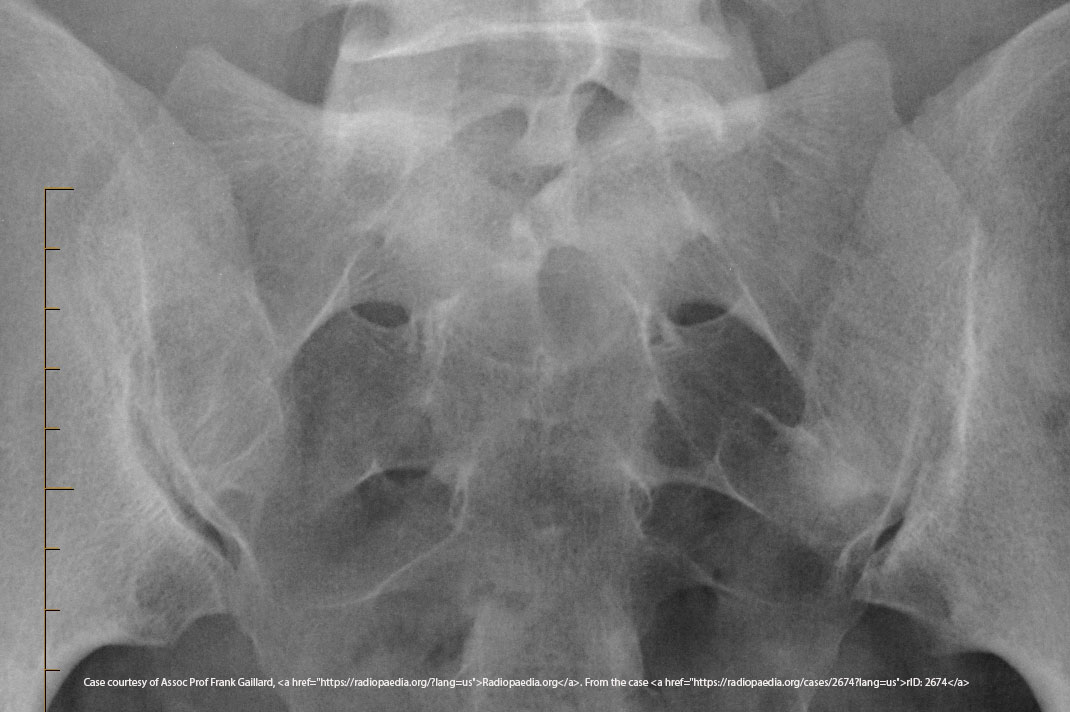

What anatomical structures does the inlet projection demonstrate?

Pelvic brim, anterior pelvis, acetabulum.

<p>Pelvic brim, anterior pelvis, acetabulum.</p>